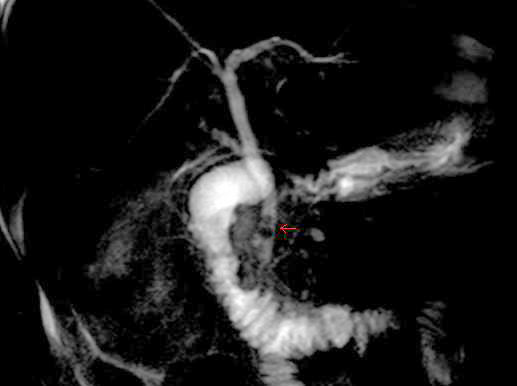

back MRCP image of two stones in the distal common bile duct

Source: CBD stones.JPG